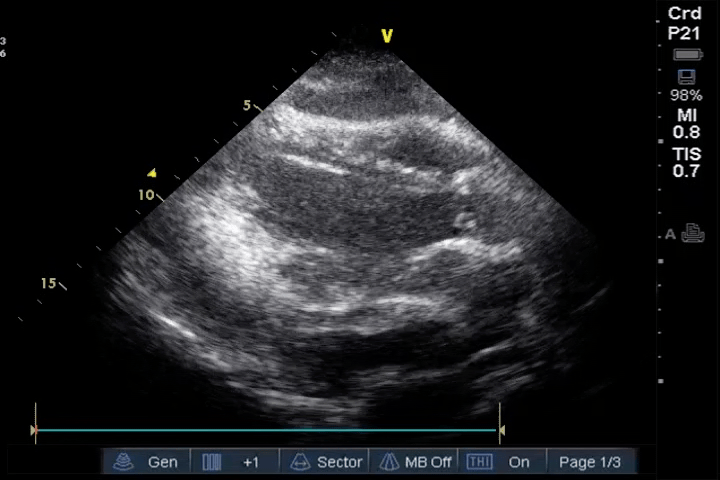

PLAX

PLAX view showing pericardial effusion with hematoma and compromised right ventricular filling: PLAX view, taken from a patient after cardiac surgery with moderate hemodynamic instability, shows a pericardial effusion surrounding the heart. A grey mass is visible within the effusion, located between the liver and the right ventricle, representing a hematoma. The right ventricle shows reduced filling during diastole, indicating compromised function, and the findings urge prompt treatment to prevent further deterioration.